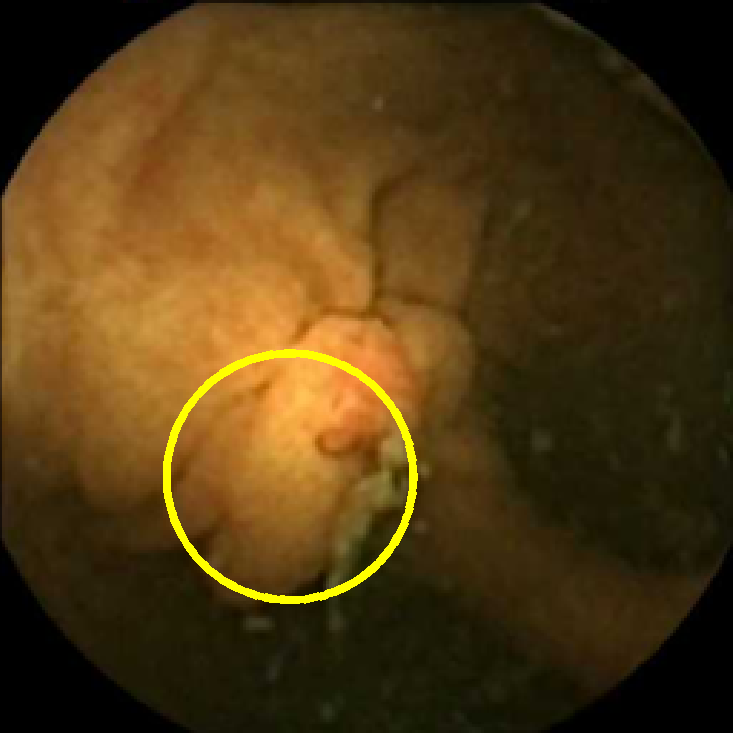

In Figure 5 we show the circles of radius corresponding to the features that were correctly classified as polyps by (29). We observe that the classifier was able to identify the polyps of a variety of shapes even in the presence of small amounts of trash liquid (first row) or when the polyps are located next to mucosal folds (rows two to four in column (c)).

The examples of incorrect classification of frames are presented in Figure 6. The first two examples show false negatives, each highlighting a possible source of classification error. The example in column (a) shows the case where the feature corresponding to the polyp was too stretched out and thus was rejected by the eccentricity criterion (21). In contrast, the feature corresponding to the polyp in column (b) has passed the combined geometric criterion (22), but the radius was below the threshold of the binary classifier. Examples in columns (c) and (d) show the two sources of possible false positives. The false positive detection in column (c) is due to insufficient illumination correction. The bright spot is not fully corrected at the pre-processing stage and subsequently generates a polyp-like feature in the mid-pass filtered frame that happens to pass through all the criteria. Finally, in column (d) a mucosal fold is classified as polyp. Note that such cases are the most difficult to deal with, as the mucosal folds can often be hard to distinguish from polyps even for a human operator.